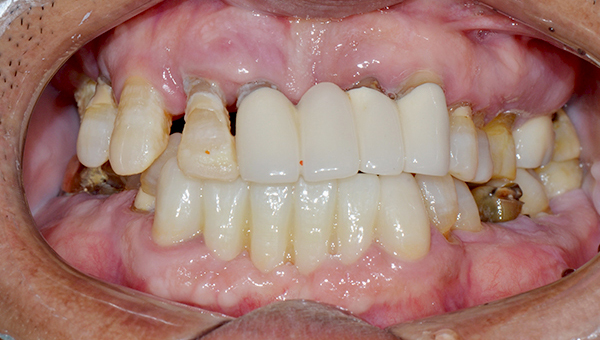

강*란 임플란트 시술 사례

전체 임플란트

2025.02.07

치료 전

2025.08.19

치료 후